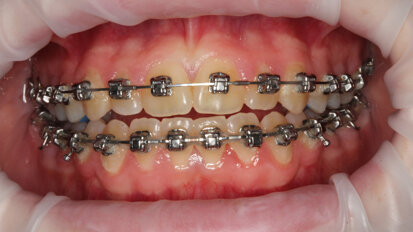

Hybridní terapie alignery